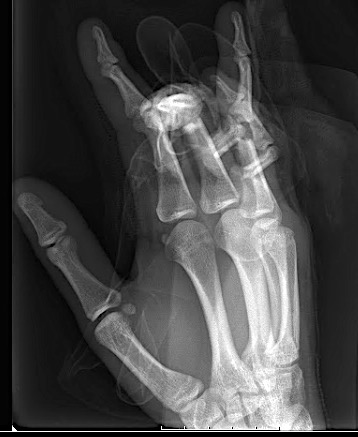

Case 2:

A 20-year-old male suffered a complex multi-digit injury of the right hand requiring revascularization and stabilization of both proximal phalanx and PIP joint fractures (Figs 5 - 8). Multiple plates, including the rotation correction plate from the 1.5 module of the VA Locking Hand System were used for fixation. The Variable Angle Locking system is ideal when only two screws, either proximal or distal, are able to be inserted due to space limitation.

One major advantage of variable angle technology in very distal phalangeal fractures is the ability to be extremely flexible with a wide range of fixation options. Freedom of implant placement assists early mobilization, vital in these complex fractures with associated soft-tissue trauma.